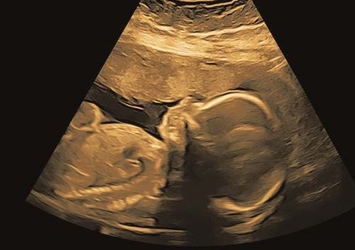

Frühe Untersuchung des kindlichen Herzens

fetale Echokardiographie

Fehlbildungsdiagnostik (Feindiagnostik)

ab der 16. Schwangerschaftswoche

Detaillierte Herzuntersuchung

fetale Echokardiographie, optimal zwischen 20.–22. Woche

3D / 4D-Ultraschall